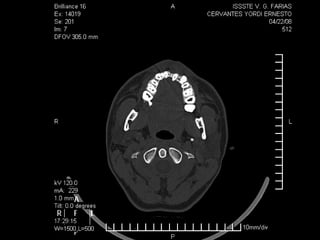

Tomografía computarizada

De seno maxilar corte sagital.

Area de implantación

Dentaria.

Material osteoconductor

para elevar el piso antral

Nuevo piso del seno y su

margen de seguridad para

contener el implante

dentario

Antro maxilar visto desde la cara interna del un hueso

Aparentemente normal

Seno maxilar aumentado de tamaño por

neumatización y edentulosis.

No compatible para aplicación de

implantes por exposición del mismo a la

luz del antro.

Colocación de material biológico o

no para aumentar el espesor del

piso y poder contener implante

dentario en un lecho de “hueso

sano”.